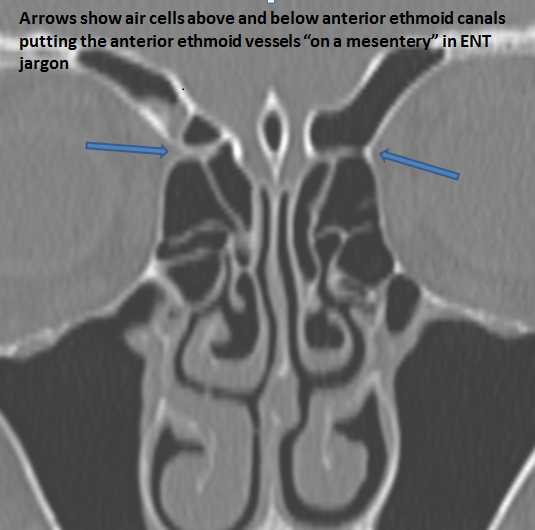

Developmental variants

The anterior ethmoid arteries are on a mesentery.